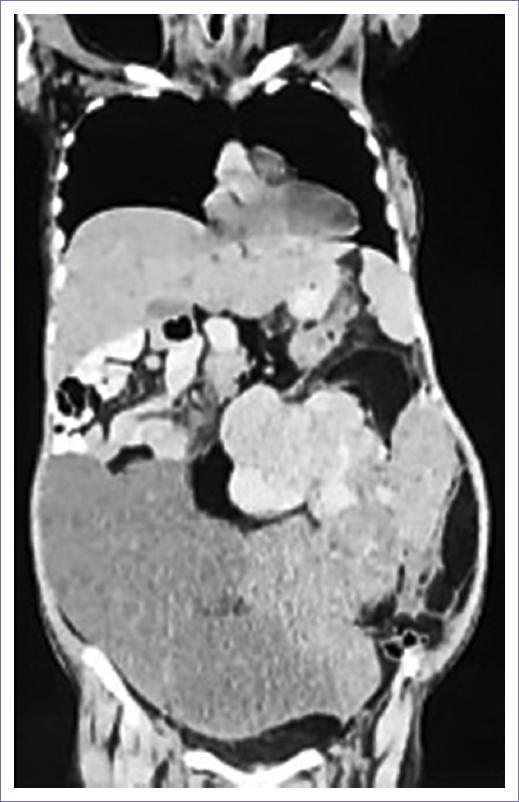

Acude para realización de nueva TC el 27 de enero de 2024, refiriendo dolor a nivel costal derecho, con aumento de perímetro abdominal y anemia, reportando hallazgos de neoformación en retroperitoneo de primario conocido 17 x 20 x 12 cm, engrosamiento focal de la pleura visceral en segmento 6, probable infiltración metastásica (Figs. 1 y 2). A su ingreso, con los siguientes estudios de laboratorio: hemoglobina 6.8 g/dl, hematocrito 24.2%, plaquetas 722,000/ul, leucocitos 10.33 x 103/ul, neutrófilos 75%, calcio 8.4 mg/dl, magnesio 2 mmol/l, sodio 136 mmol/l, potasio 4.1 mmol/l, cloro 96.7 mmol/l, glucosa 102, creatinina sérica 0.4 mg/dl, nitrógeno ureico en sangre 5 mg/dl, tiempo de protrombina 14.7 s, ratio internacional normalizado 1.3, tiempo de tromboplastina parcial 33.9 s, CA 19-9 5.7 Ul/ml, antígeno carcinoembrionario 0.5 ng/ml.

Figura 1 Tomografía contrastada con lesión en cavidad abdomino-pélvica y retroperitoneo de aspecto tumoral.